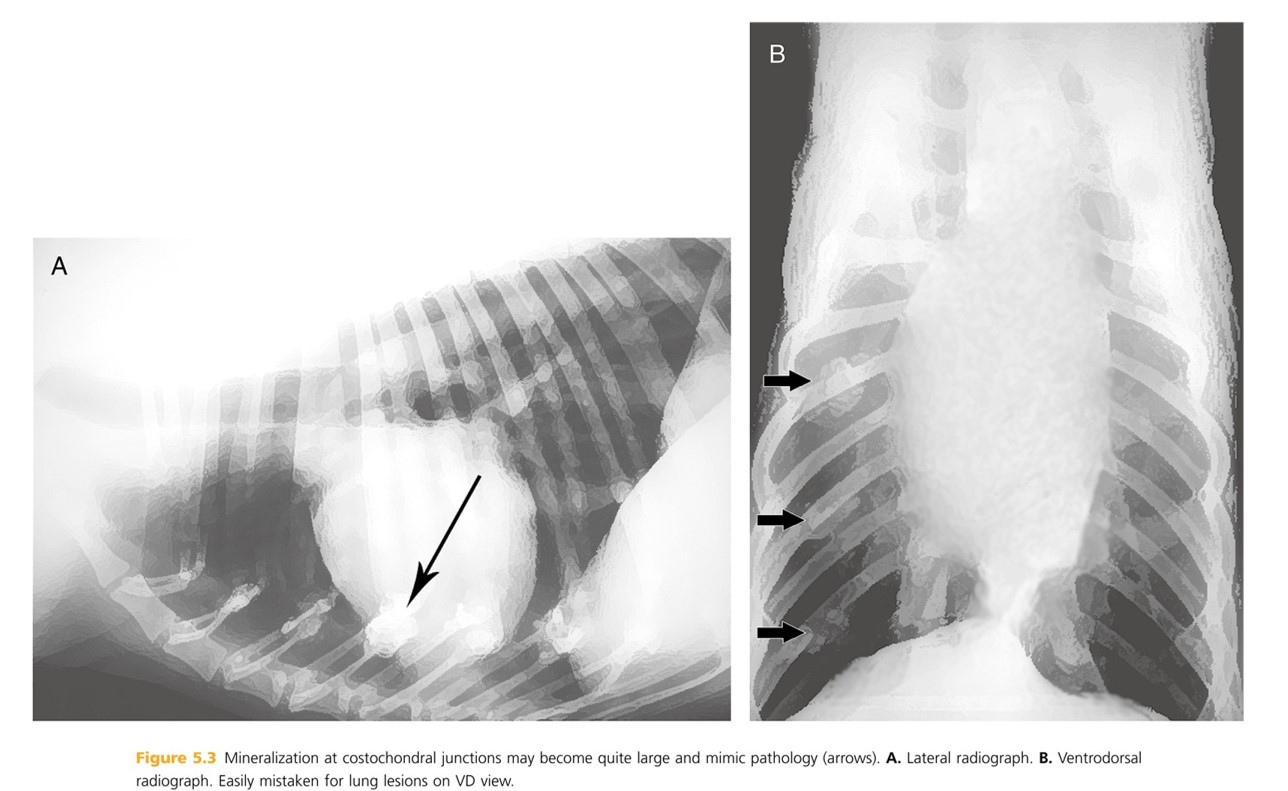

Mineralization at costochondral junctions may become quite large (especailly in ____________ and ____ large breed dogs.

Page 277 chondrodystrophic and older large breed dogs.